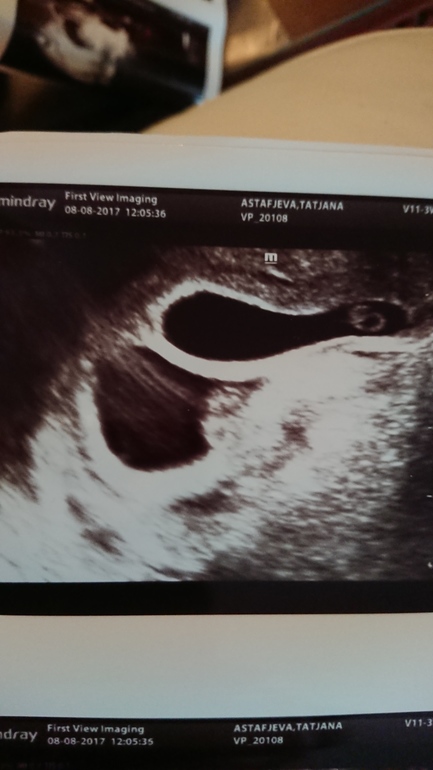

А вот неделю назад